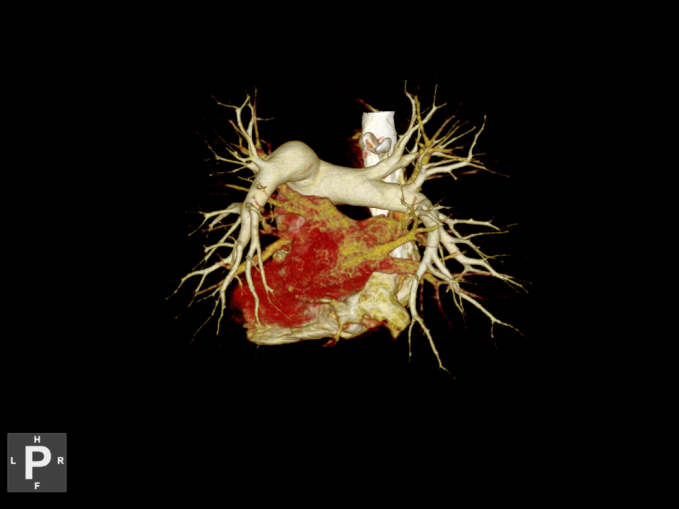

术前CTA

患者取平卧位,留置导尿,气管插管全麻达成后,常规消毒铺巾,超声引导下穿刺右股静脉放置6F鞘,术中造影显示:下腔静脉通畅,未见造影剂充盈缺损,双肺动脉主干及分支栓塞,肺动脉显影差。

取栓前造影

导丝导管配合超选进入右肺动脉分支远端,交换硬导丝,更换腾复肺动脉取栓导管,通过负压抽吸取除大部分右肺动脉血栓,同法行左肺动脉取栓,再次造影显示双肺动脉主干血流通畅,远端分支显影可。

术后次日转回普通病房。术后第4天出院。术后第27天下腔静脉滤器取出。术后1月复查肺动脉CTA示:主肺动脉、左右肺动脉干及近段部分较大分支走行正常,右肺叶间动脉见少许充盈缺损影,两肺动脉栓塞基本好转。

术后CTA

术后1月CTA复查